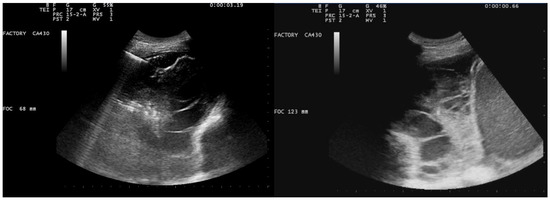

After a chest CT scan, which showed a massive effusion, the patient underwent a thoracoscopic lavage of the left pleural cavity without any complications. At the end of the surgery, two left thoracic drains were left in place, through which repeated irrigation of the pleural cavity with urokinase was performed under serial US and radiological monitoring in the following days (Figure 4). At the same time, empiric antibiotic therapy with piperacillin/tazobactam and teicoplanin was initiated. During his hospitalization, the patient remained stably apyretic, with a progressive improvement of pulmonary gas exchange and the normalization of his inflammation biomarkers. Subsequently, the FiO2 was gradually titrated until the complete discontinuation of oxygen therapy.

In this scenario, fibrinolysis was performed after a uniportal VATS because of the persistence of fibrinous septa visualized using US and the slow outflow of fluid into the drainage bag. The irrigation of the pleural cavity was conducted with 200,000 UI of urokinase in 50 mL of saline solution. This was followed by the closure of the chest drain for 2–4 h, and then it was reopened. Irrigation was performed every 48 h for 3 days. On day 5, the absence of fibrinous septa and the small amount of fluid on the patient’s chest US allowed for the removal of the drain and his discharge from the hospital.

Figure 4. Complex and septated pleural effusion after VATS treated with IPFT.